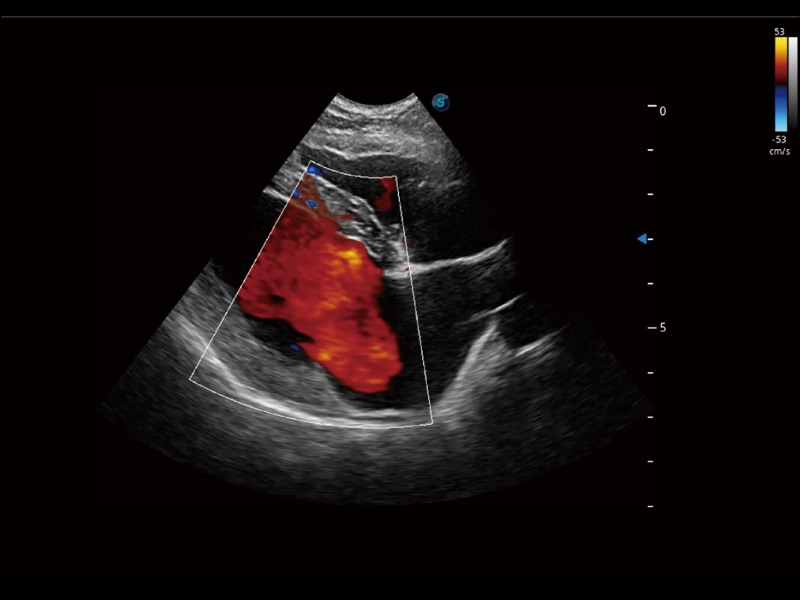

采用紅、橙、黃、綠、青、藍、紫這七種肉眼最為敏感的色彩,直觀地顯示組織內(nèi)血流灌注的時間先后信息,更精準捕捉血流灌注走行細節(jié)。